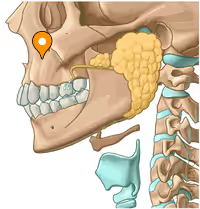

Which one would probably impact your looks more if it was deeper

Which one would probably impact your looks more if it was deeper